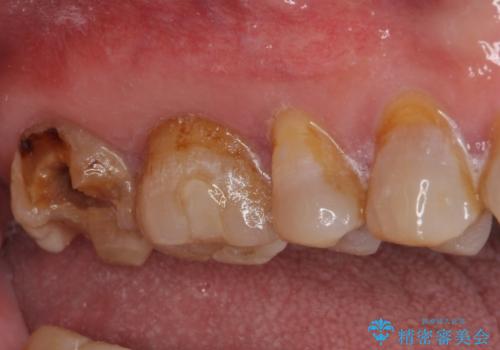

- 銀歯が外れてしまったとのことで来院された患者様です。

上顎奥の粘膜に近い部分で、外れた銀歯の下には大きく虫歯が広がっていました。

虫歯をしっかりと取り除き、ゴールドインレーにて修復することとしました。